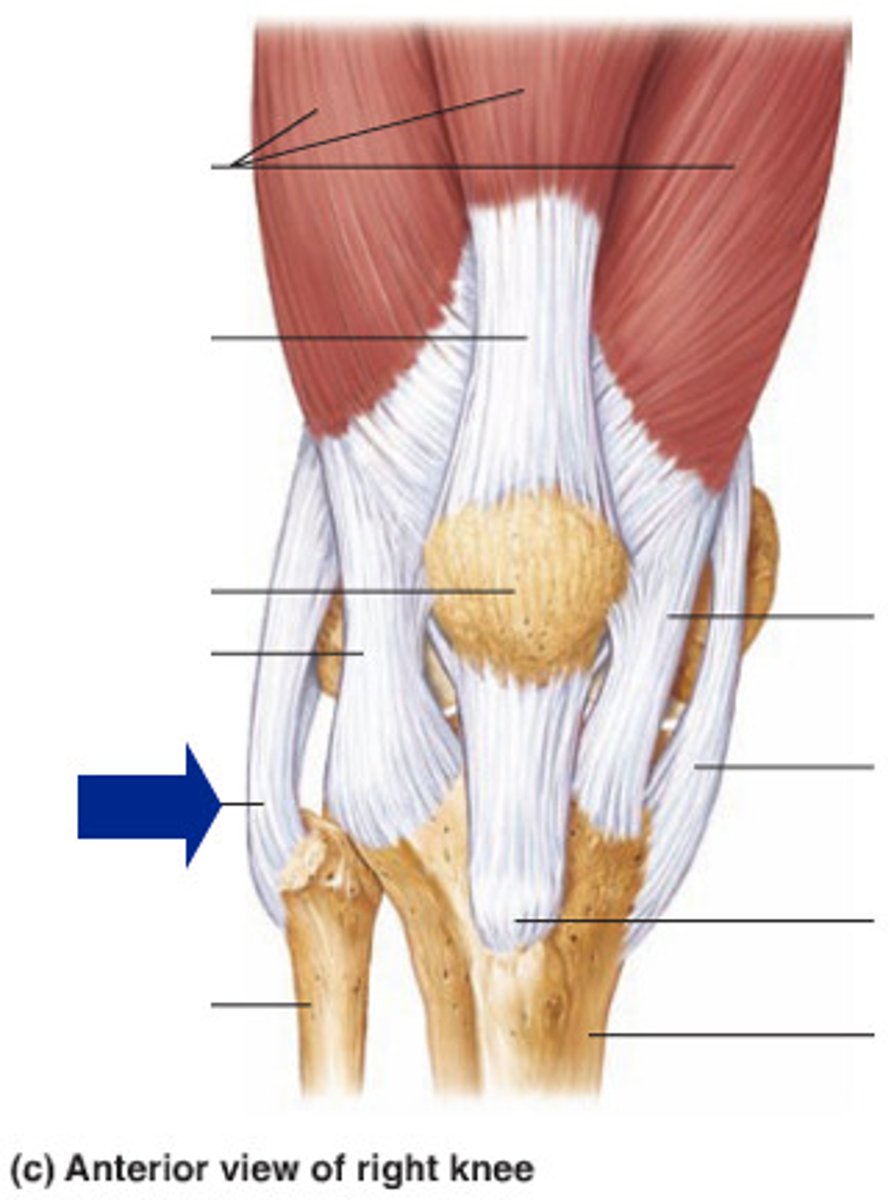

Quadriceps tendon

Patellar ligament

Medial meniscus

Lateral meniscus

Anterior cruciate ligament

Posterior cruciate ligament

Medial (tibial) collateral ligament

Lateral (fibular) collateral ligament